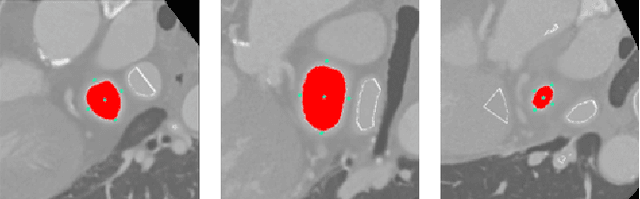

In preoperative planning of left atrial appendage closure (LAAC) with CT angiography, the assessment of the appendage orifice plays a crucial role in choosing an appropriate LAAC device size and a proper C-arm angulation. However, accurate orifice detection is laborious because of the high anatomic variation of the appendage, as well as the unclear orifice position and orientation in the available views. We propose an automatic orifice detection approach performing a search on the principal medial axis of the appendage, where we present an efficient iterative algorithm to grow the axis from the appendage to the left atrium. We propose to use the axis-to-surface distance of the appendage for efficient and effective detection. To localize the necessary initial seed for growing the medial axis, we train an artificial localization agent using an actor-critic reinforcement learning approach, defining the localization as a sequential decision process. The entire detection process takes only about 8 seconds, and the variance of the detected orifice with respect to annotations from two experts is calculated to be significantly small and less than the inter-observer variance. The proposed orifice search on the medial axis of the appendage comparing only its distance from the surface provides a simple, yet robust solution for orifice detection. While being the first fully automatic approach and providing a detection error below the inter-observer difference, our method improved the detection efficiency by eighteen times compared to the existing solution, therefore, can be potentially useful for physicians.